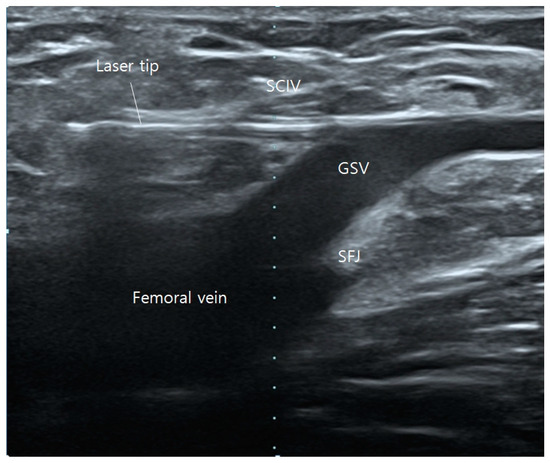

After ablating one of the tributaries, the fiber tip is then brought down to the GSV and moved forward to the SFJ, ablating the GSV until below the knee (Figure 3 and Figure 4), The other left-over tributary observed on ultrasound examination on the next follow-up is treated with foam sclerotherapy.

Figure 3. Operative ultrasonography of saphenofemoral junction (SFJ). Juxta-high laser tip placement.

Figure 4. Flush ablation performed on great saphenous vein (GSV) at the saphenofemoral junction (SFJ) and intact femoral vein.